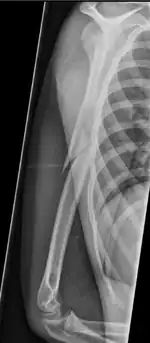

| Pathological fracture of the humerus in a patient with metastasis of renal cell carcinoma | |

A pathologic fracture is a bone fracture caused by weakness of the bone structure that leads to decrease mechanical resistance to normal mechanical loads.[1] This process is most commonly due to osteoporosis, but may also be due to other pathologies such as cancer, infection (such as osteomyelitis), inherited bone disorders, or a bone cyst. Only a small number of conditions are commonly responsible for pathological fractures, including osteoporosis, osteomalacia, Paget's disease, Osteitis, osteogenesis imperfecta, benign bone tumours and cysts, secondary malignant bone tumours and primary malignant bone tumours.

Pathological fractures present as a chalkstick fracture in long bones, and appear as a transverse fractures nearly 90 degrees to the long axis of the bone. In a pathological compression fracture of a spinal vertebra fractures will commonly appear to collapse the entire body of vertebra.